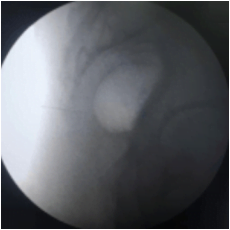

This procedure is performed with the patient in a prone position on the Operating table. Some practitioners like to prepare patients with laxatives the night before. With fluoroscopic guidance, a thin spinal needle is advanced through the sacrococcygeal hiatus. Needle placement is confirmed and dye spread is checked under fluoroscopy. Medication is delivered at the site of the Ganglion of Impar. This helps in blocking the sacrococcygeal plexus of nerves.

Lateral view

Intraop fluoroscopy image of ganglion impar injection